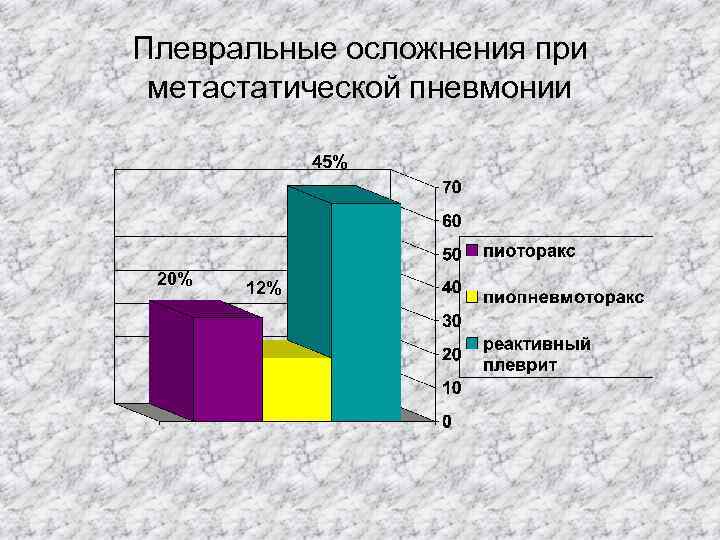

Плевральные осложнения при метастатической пневмонии 45% 20% 12%

Плевральные осложнения при метастатической пневмонии 45% 20% 12%